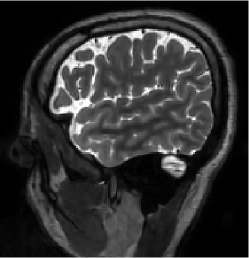

IV-B Data for training and testing the algorithm

The MRI data used for this study were acquired using a 3D T2 CUBE sequence with Cartesian readouts using a -channel head coil. The matrix dimensions were 256 232 208 with mm isotropic resolution. Fully sampled multi-channel brain images of five volunteers were collected out of which data from four subjects were used for training, while the data from the fifth subject were used for testing. Since the readout is fully sampled, we evaluated the inverse Fourier transform of each readout. We retrospectively undersampled the phase encodes to train and test the framework; we note that this approach is completely consistent with a future prospective acquisition, where a subset of phase encodes can be pre-selected and acquired. All the experiments were performed with variable-density Cartesian random sampling mask with different undersampling factors mentioned at their use.

Out of the total slices for each subject, we selected slices that had images of parts of the anatomy for training. The coil sensitivity maps were estimated from the central k-space regions of each slice using ESPIRiT [42] and were assumed to be known during experiments. Thus, the training data had dimensions in as and testing data had dimensions . The testing was performed on slices out of available for the test subject since the initial and the last slices did not have any brain region but noise. To reduce the sensitivity to acquisition settings, including undersampling patterns, we used different variable density Cartesian pseudo-random sampling masks for each training slice. The same sampling mask was used for the data from all coils of the same slice. The undersampling factors are mentioned at their use in the experiments. The sampling masks used during the testing were different from the ones used during the training.

We show the intermediate steps of the reconstruction scheme at two different iterations in Fig. 5. The top row correspond to the 16-fold random undersampling setting. Please refer to Fig. 1(c) for an illustration of the unrolled network architecture. At each iteration, the input is fed to the plug-and-play CNN, which extracts the alias/noise components . We note that the noise/alias terms estimated at each iteration are different, with the variance within the brain regions decreasing as iterations progress. The addition of the noise components to the input yields the denoised output . The data consistency block, denoted by combines the denoised outputs with the other terms to yield . The process is repeated for ten iterations that gradually improve the reconstruction quality and decrease the noise as evident from the figure.

The end-to-end training strategy ensures that the CNN learns the information that is complementary to the ones obtained from coil sensitivity and data consistency information. Fig. 5 also shows the reconstruction outputs extracted from intermediate layers in a super-resolution setting. It is evident from Figures 5(j) and 5(n) that network is able to predict the alias patterns and the aliasing decays as the number of iterations increase. Note that the same network was used in both the experiments, which shows the ability of the same network to remove alias patterns that are dramatically different.

Figures 7 and 8 visually compare two different slices at 4x and 8x accelerated data acquisition in the presence of Gaussian noise of . The testing slices are from a subject, whose data was not used for training. It is evident from the zoomed portions that the reconstruction quality by the proposed method is better than the techniques compared against.